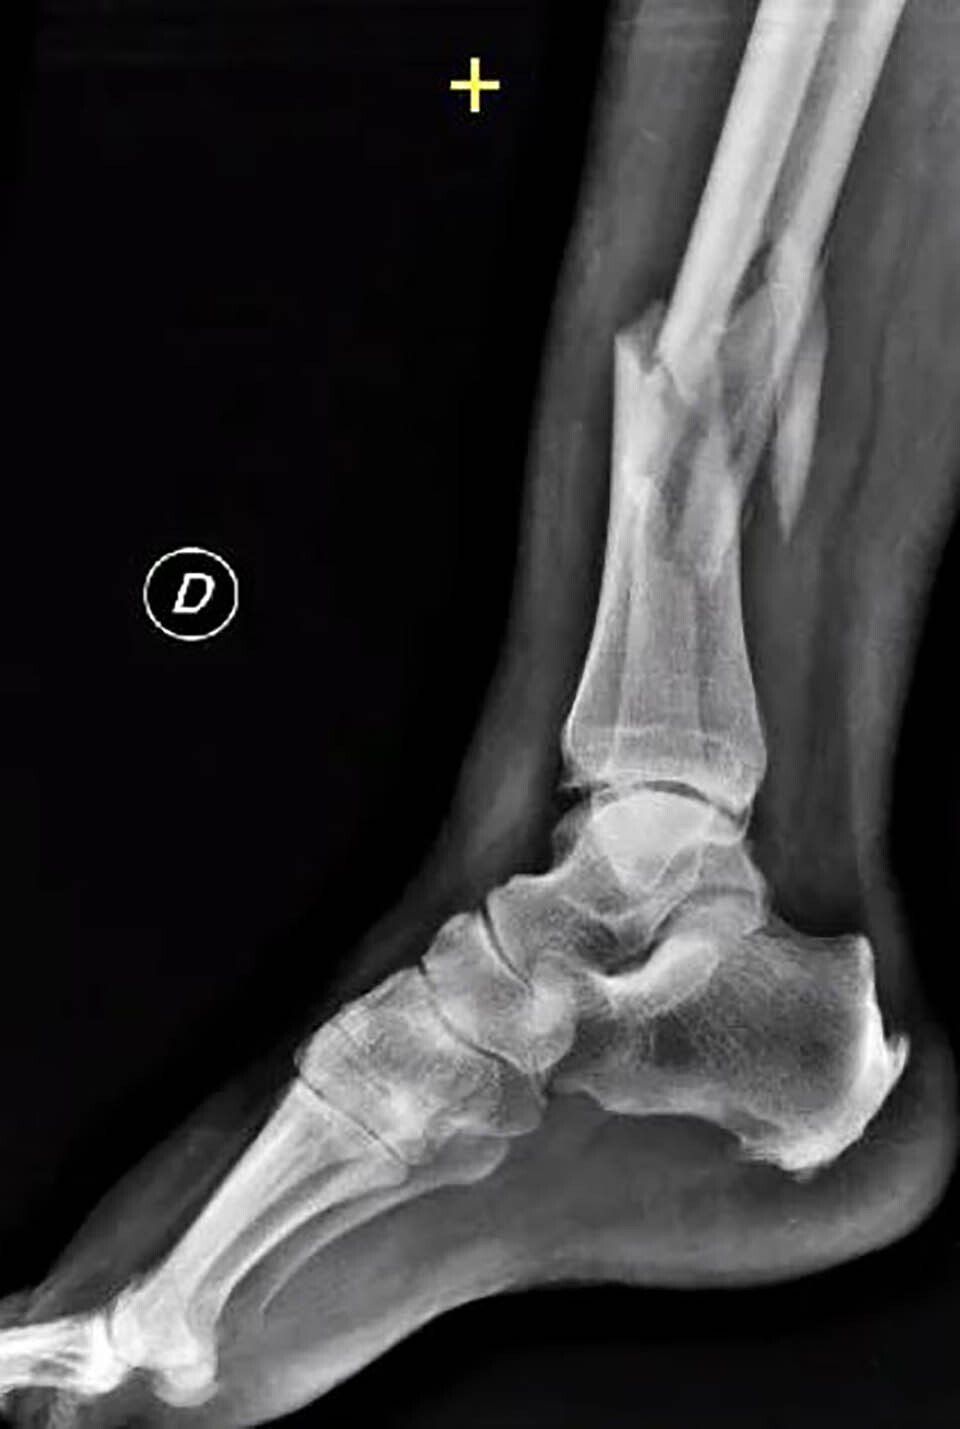

Pseudoarthrosis can be radiographically classified as atrophic or hypertrophic. The former is associated with poor vascular supply, and the latter with a lack of mechanical stability. In atrophic pseudoarthrosis, there are few signs of bone apposition, sometimes there may be resorption of the ends, and usually, the bone segment is mobile.

In hypertrophic pseudoarthrosis, there is an increase in bone callus at the fracture site, with signs of consolidation without complete healing, and usually, there is less mobility.

Other bones, like the femoral head, talus, and scaphoid, have limited blood supply. In these cases, a fracture can cause a disruption in the vascular system, increasing the risk of pseudoarthrosis.

Finally, other bones, like the tibia, have moderate blood supply as they are covered by a thin layer of soft tissues. Severe trauma can compromise both internal and external vascularisation, increasing the risk of pseudoarthrosis.